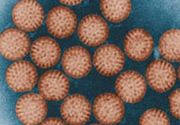

| 2021年7月26日 (一) 20:01 | 轮状病毒.jpg (文件) |  |

63 KB | 77921020 | Uploaded with SimpleBatchUpload | 3 |